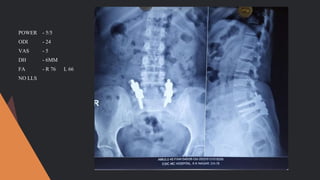

POWER - 5/5

ODI - 24

VAS - 5

DH - 6MM

FA - R 76 L 66

NO LLS